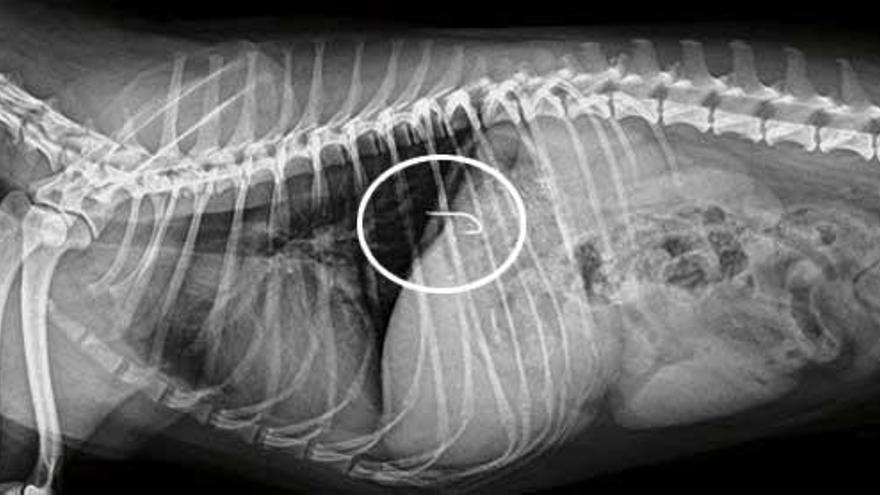

Nicht nur Hunde, auch Angelhaken gehören an die Leine und sollten nicht frei in der Gegend gelassen werden. Leider ist es kein Einzelfall. Allein im Molinar-Viertel in Palma de Mallorca mussten seit Jahresbeginn bereits sechs Hunde operiert werden, weil sie von Anglern achtlos weggeworfene und noch mit Ködern versehene Angelhaken verschluckt hatten.

Es komme immer wieder vor, dass Angler ihre Köderbox auf dem Boden stehen ließen. Darin befinden sich neben aufgeweichtem Brot, Essensresten und Würmern eben auch oft Haken. Hunde, die von dem Essensgeruch angelockt werden, verschlucken die spitzen Metallhaken. Die dann notwendige Operation ist nicht nur für die Tiere schmerzhaft und gefährlich. Sie kostet die Besitzer auch - je nach Hunderasse und Komplikationen - zwischen 400 und 1.000 Euro.